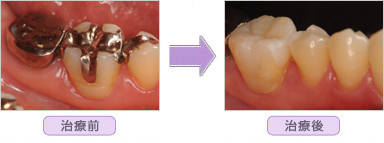

ハイブリットセラミックインレーの治療紹介

■ 右下臼歯部1本セラミック T.S様 27歳 女性

■ 右下臼歯部2本セラミック H.O様 35歳 女性

■ 右下臼歯部3本セラミック S.M様 36歳 女性

■ 左上臼歯部2本セラミック A.K様 36歳 女性